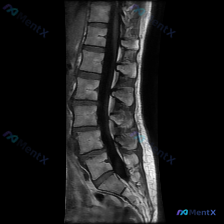

只看这张腰椎MRI矢状位T2像,你会先关注什么?

整理了一份腰椎MRI T2加权像(矢状位)的影像分析资料,先不说临床背景,大家第一眼看到这张影像,会先关注哪些征象?

目前能看到的客观表现有这些方向(可能不全):

- 椎间盘信号和形态

- 椎管和硬膜囊

- 脊柱序列和曲度

- 椎体终板和骨髓

这份资料里有一个点特别提醒不要过度诊断,回头看确实容易踩坑。